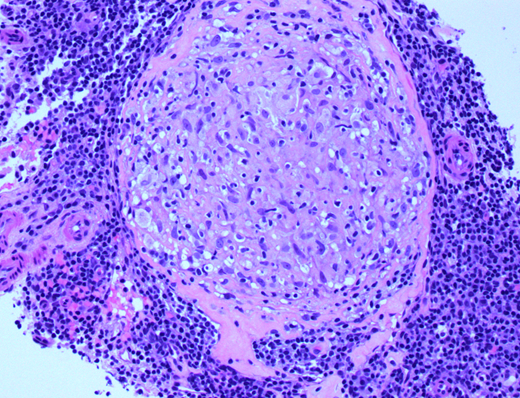

We present the case of a 75-year-old woman who presented with chronic cough and dyspnea of several years' duration. She was found to have fluctuating lung infiltrates on serial imaging studies. A bronchial biopsy revealed chronic inflammation, and no evidence of infection. She was then treated with oral steroids with a transient benefit. However, the infiltrate and symptoms recurred, therefore 8 months later, she underwent repeat imaging. This showed a relapse of the infiltrate and enlarged mediastinal lymphadenopathy. The lung infiltrate was biopsied (percutaneously). This demonstrated a MALT lymphoma. Imaging studies done for staging showed a large retroperitoneal lymph node. A biopsy of this node revealed non-caseating granulomas, consistent with sarcoidosis. Chemotherapy with bendamustine and rituximab was initiated for therapy of the MALT lymphoma.

A rare association between pulmonary MALT lymphoma and underlying inflammation caused by sarcoidosis has been previously described. In our patient, sarcoidosis was diagnosed in a biopsy of a retroperitoneal lymph node, but we suspect that there is likely involvement of the mediastinal nodes.